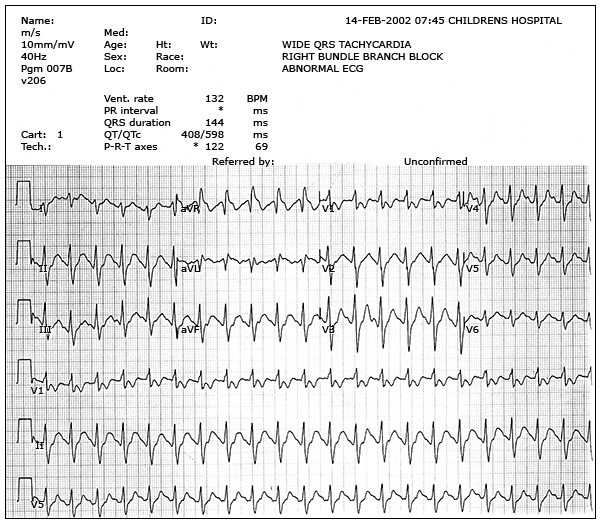

These are a series of electrocardiograms (ECGs) obtained from a patient with tricyclic antidepressant overdose. The first (above) shows the initial ECG demonstrating QRS interval prolongation and characteristic changes in AVR. The second (Severe cardiac toxicity) shows worsening changes consistent with progression of cardiac toxicity. Note the increases in the QRS interval and the R wave in AVR. The third (After treatment) shows narrowing of the QRS complex but persistent right axis deviation of the terminal 40 milliseconds following the initiation of treatment. The final ECG (Resolution) shows complete resolution of interval changes related to toxicity.

ECG with TCA poisoning: Severe cardiac toxicity